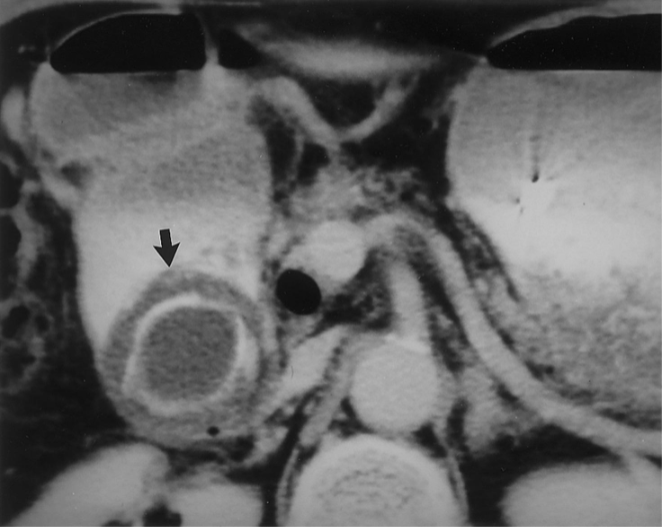

Magnetic Resonance Cholangiopancreatography (MRCP)

Noninvasive

Alternative if US negative

Common bile duct stone